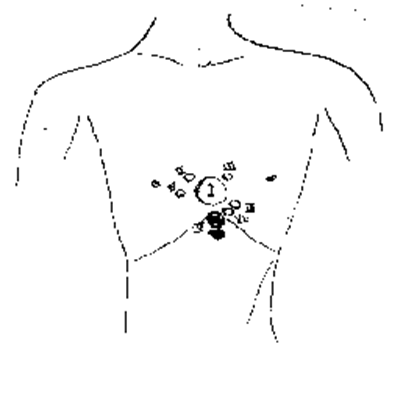

图一,在一个印度青年胸部的浅色素区域。他儿童时声称记得一个叫Maha Ram的去世男人的生平,Maha Ram在近距离内被用霰弹枪开枪打死。(图片来源:childpastlives)

图二,图中的圈显示了Maha Ram的枪伤区域,供与图一比较。该图来自Maha Ram的验尸报告。(图片来源:childpastlives)

如果胎记和伤痕在同一解剖位置的10平方厘米内,则我们认为胎记和伤痕是令人满意地一致的。实际上很多胎记和伤痕比这个范围要接近得多。在49个案例中我们得到了医学报告(通常为验尸报告),43个案例(88%)中伤痕和胎记是令人满意地或更好地一致的,6个案例中不是满意地一致。有几个因素可以来解释这些不一致,我在其他出版物中有解释(将要发表)。图一是在一个印度青年胸部的一个胎记(一个浅色素区域)。他儿童时声称记得一个叫Maha Ram的去世男人的生平,Maha Ram在近距离内被开枪打死。图二的圈显示了法医记录的枪伤位置,(圈是一个印度医生绘制,他和我一起研究了验尸报告)。